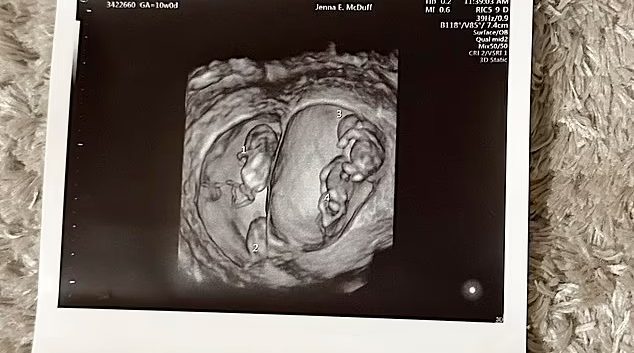

1 во 70 милиони: 23 годишна мајка којашто е бремена за прв пат, носи два пара идентични близнаци

Една мајка, била запрепастена кога за прв пат открила дека е трудна со два пара идентични близнаци. Идните родители, Ебони Апс, 23 и Џејден, 21, кои потекнуваат од Кемпси, Нов Јужен Велс, Австралија, биле во тотално неверување кога откриле дека очекуваат исклучително редок сет на четворки. Откако претходно доживеала два спонтани абортуси …